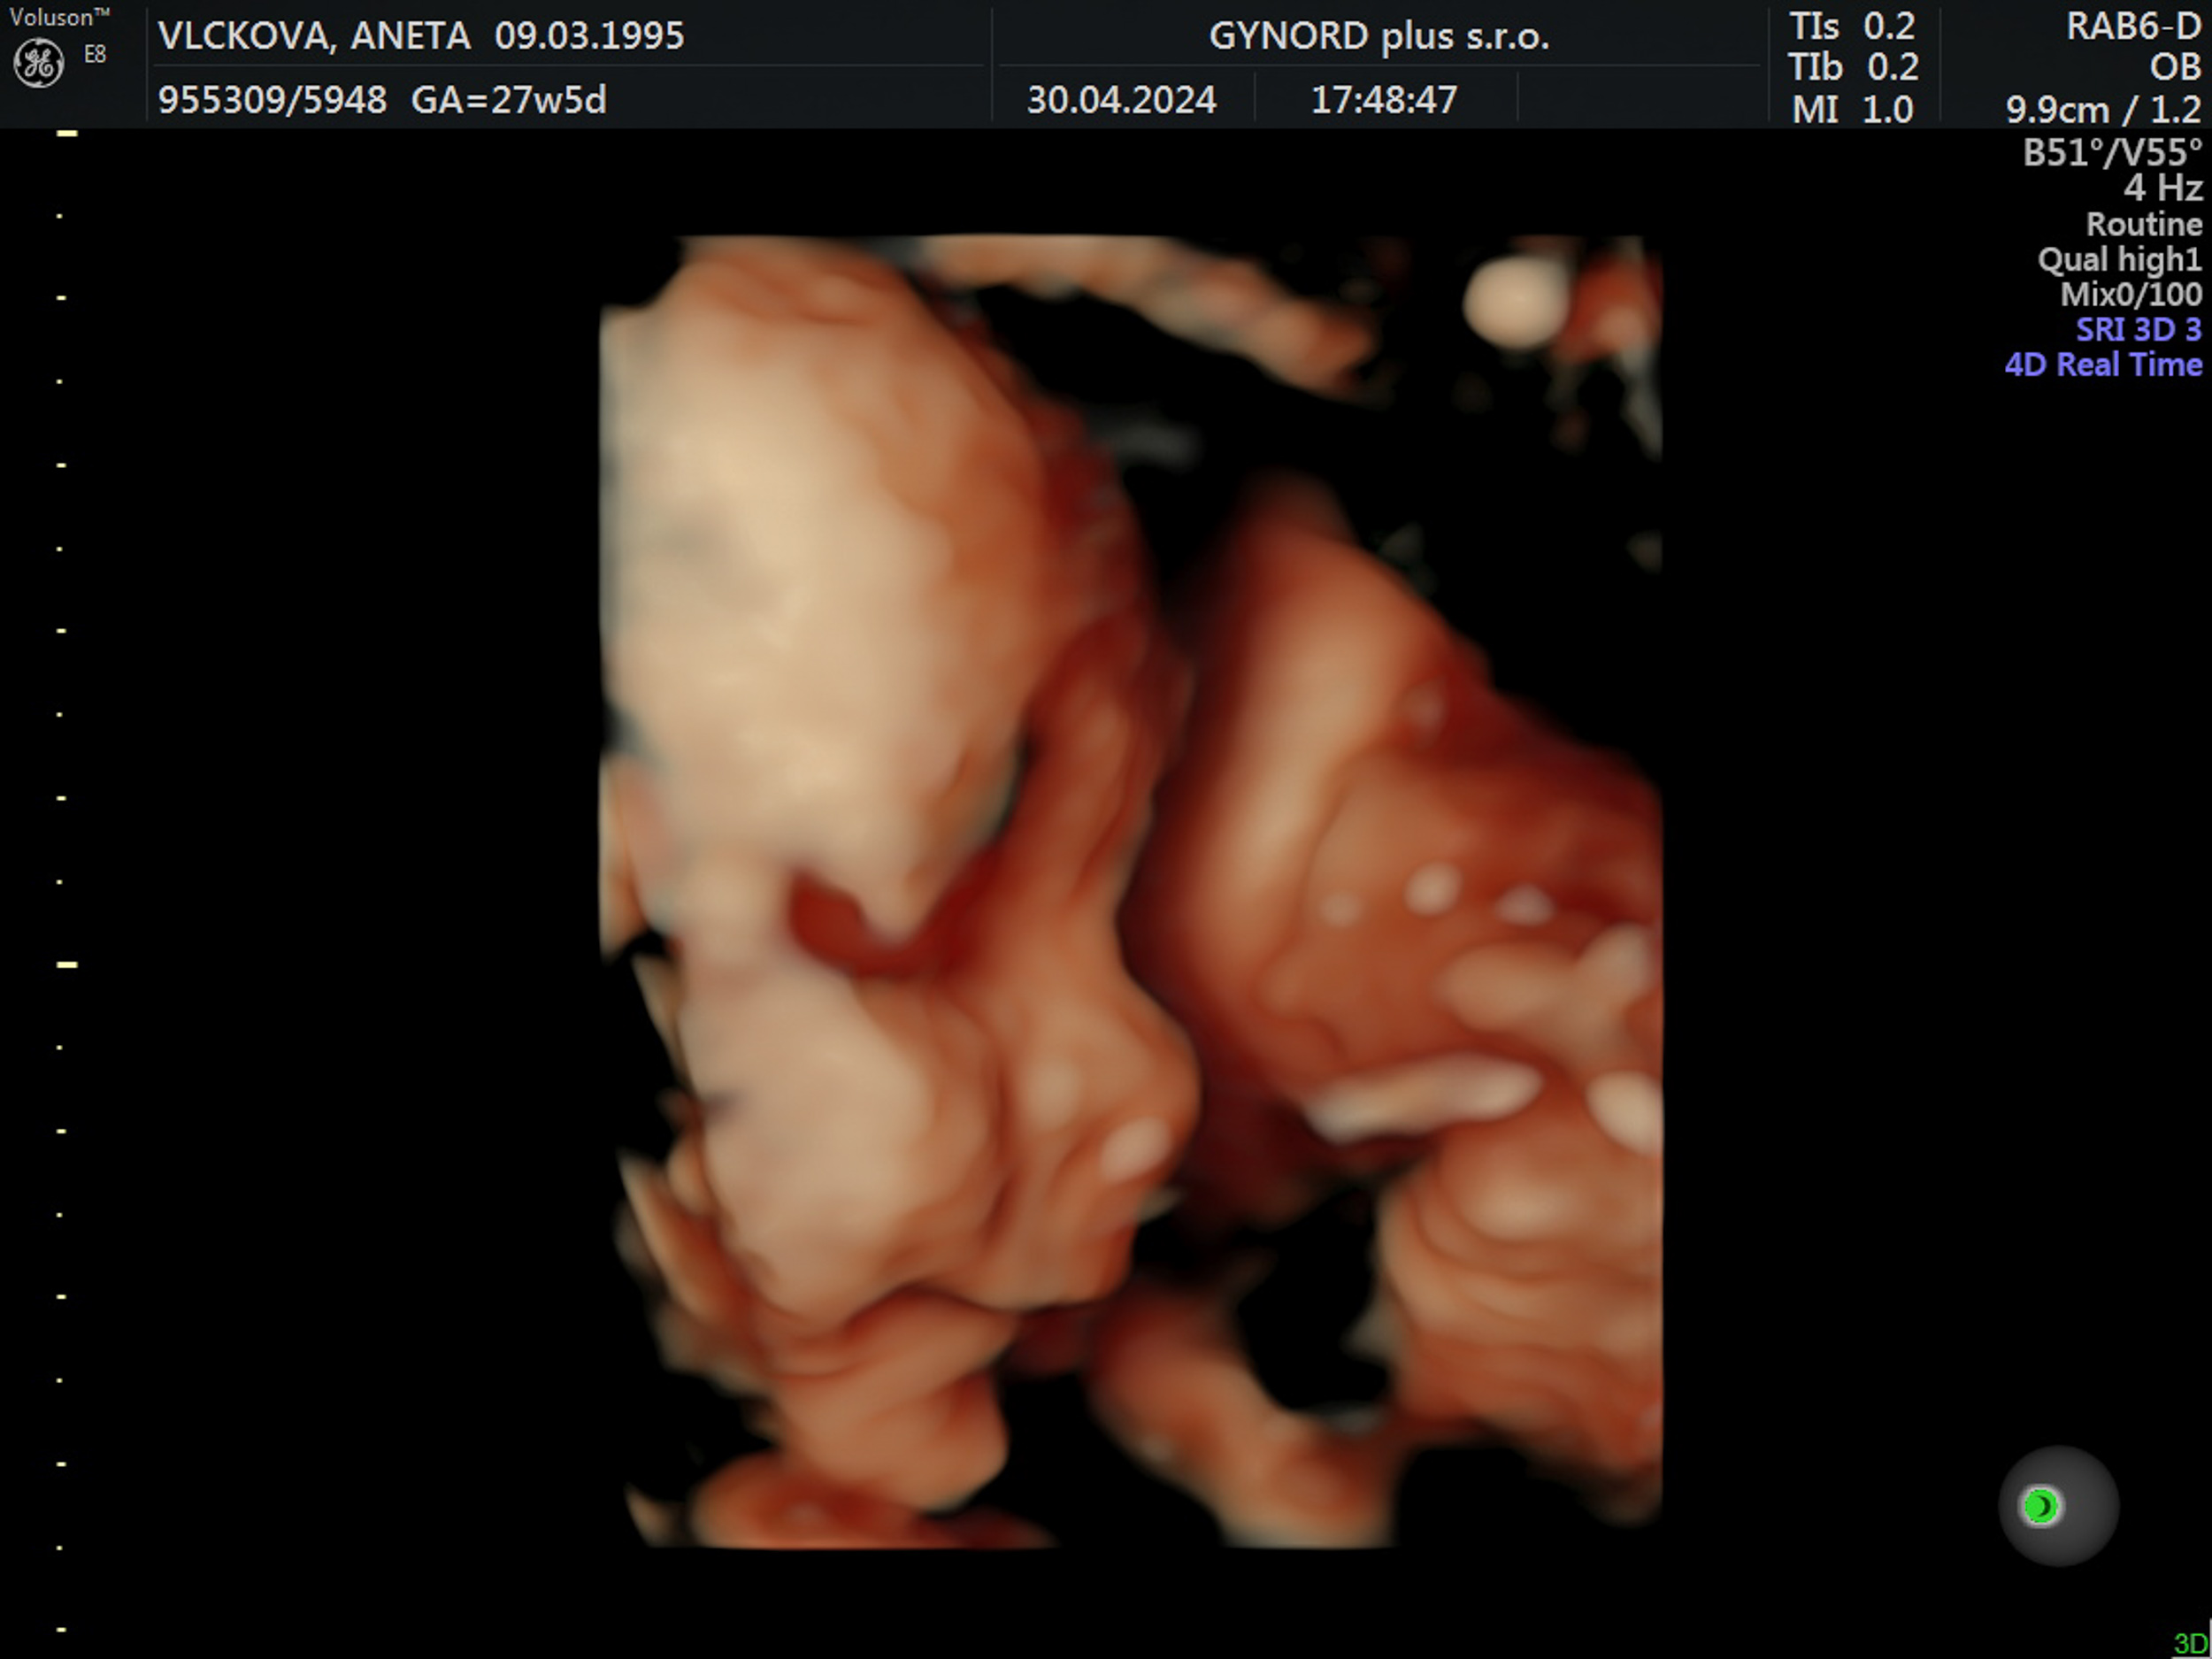

Tomášek - ještě v bříšku

2023-09-26